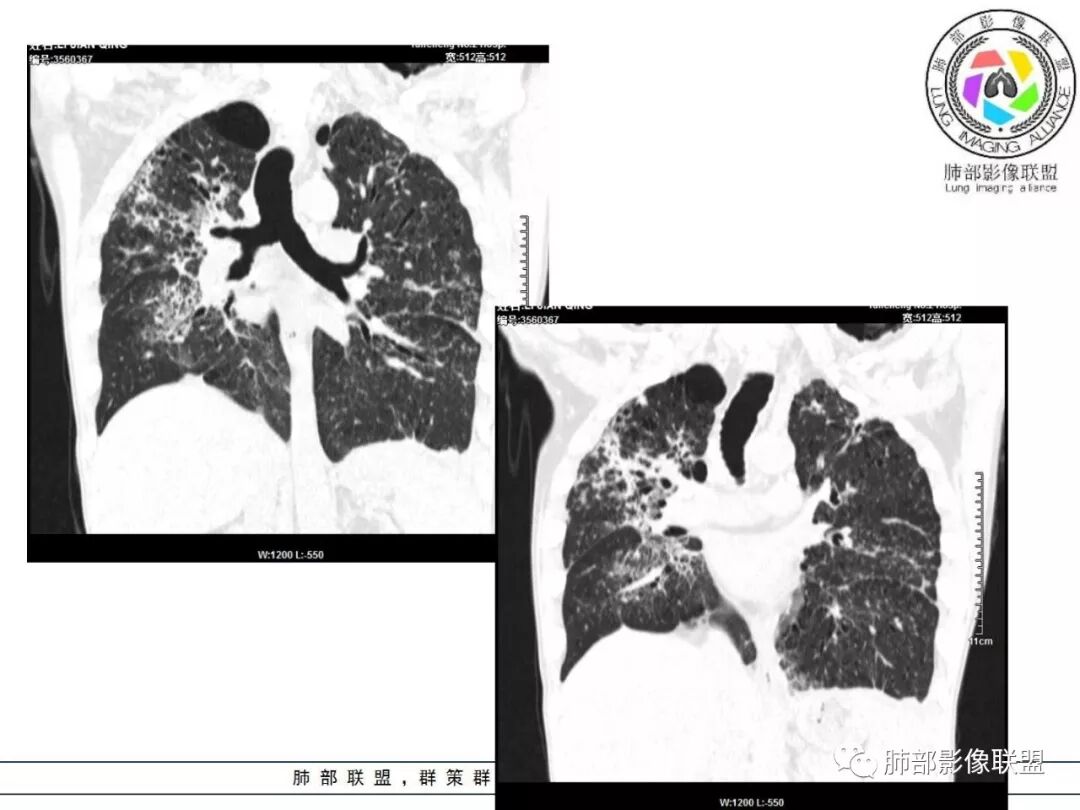

双肺间质性病变,中央间质增厚,胸膜下间质增厚,左侧胸膜肥厚,胸廓变小,肋间隙变窄。

对,大的支气管血管周围

胸部CT:两肺弥漫病灶,磨玻璃影,少许实变,部分累及胸膜,磨玻璃区可见囊?少许胸腔积液,两肺可见结节,支气管血管束增粗,小叶间隔增厚,支气管走形有扭曲扩张,可见纤维化。气肿、大泡。考虑:感染性病变,PCP?查下HIV,CD4,G等。鉴别结核、结缔组织病肺浸润。

胸部CT:两肺弥漫病灶,中央间质分布为主,部分位于胸膜及叶间裂旁,磨玻璃影,斑片影,部分实性结节,肺气囊,支气管血管束增粗,小叶间隔增厚,叶间裂不均匀增厚,支气管走形有扭曲扩张,可见纤维化、气肿、大泡。考虑:LIP加MALT。鉴别PLCH、PCP、结核、结缔组织病肺浸润。

双肺弥漫性病变,多发磨玻璃密度及小叶间隔增厚,大部分沿支气管血管束分布,伴支气管轻度扩张,以午后及晚上发热为主,考虑感染性病变,间质性结核可能大,另双肺多发肺气囊,LIP待排

病变一般沿血管支气管束分布或小叶分布,一般上肺多于下肺(这与常见继发性肺结核分布相若)。

常会伴有其他继发性肺结核病灶,如斑片影、结节影,树芽征,新旧不等改变。

2. 肺气肿背景(小叶中心性肺气肿);双肺多发病灶整体沿血管支气管束及胸膜下分布,以上叶及下叶背段分布为主,有实变及GGO,边界清楚,有树芽,小叶间隔及中央间质增厚,叶间裂见到多发结节,部分支气管不规则牵拉扩张,提示病灶纤维化明显,结合临床病史,考虑病灶为间质性感染,肺门及纵隔内有钙化淋巴结,小叶间隔结节,考虑淋巴道增值性疾病可能,综合常规要怀疑间质性肺结核。